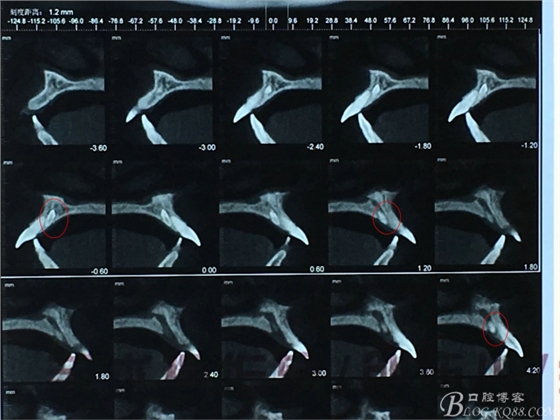

圖4.CBCT檢查:21根尖區(qū)的多生牙位于鼻腭管內(nèi)